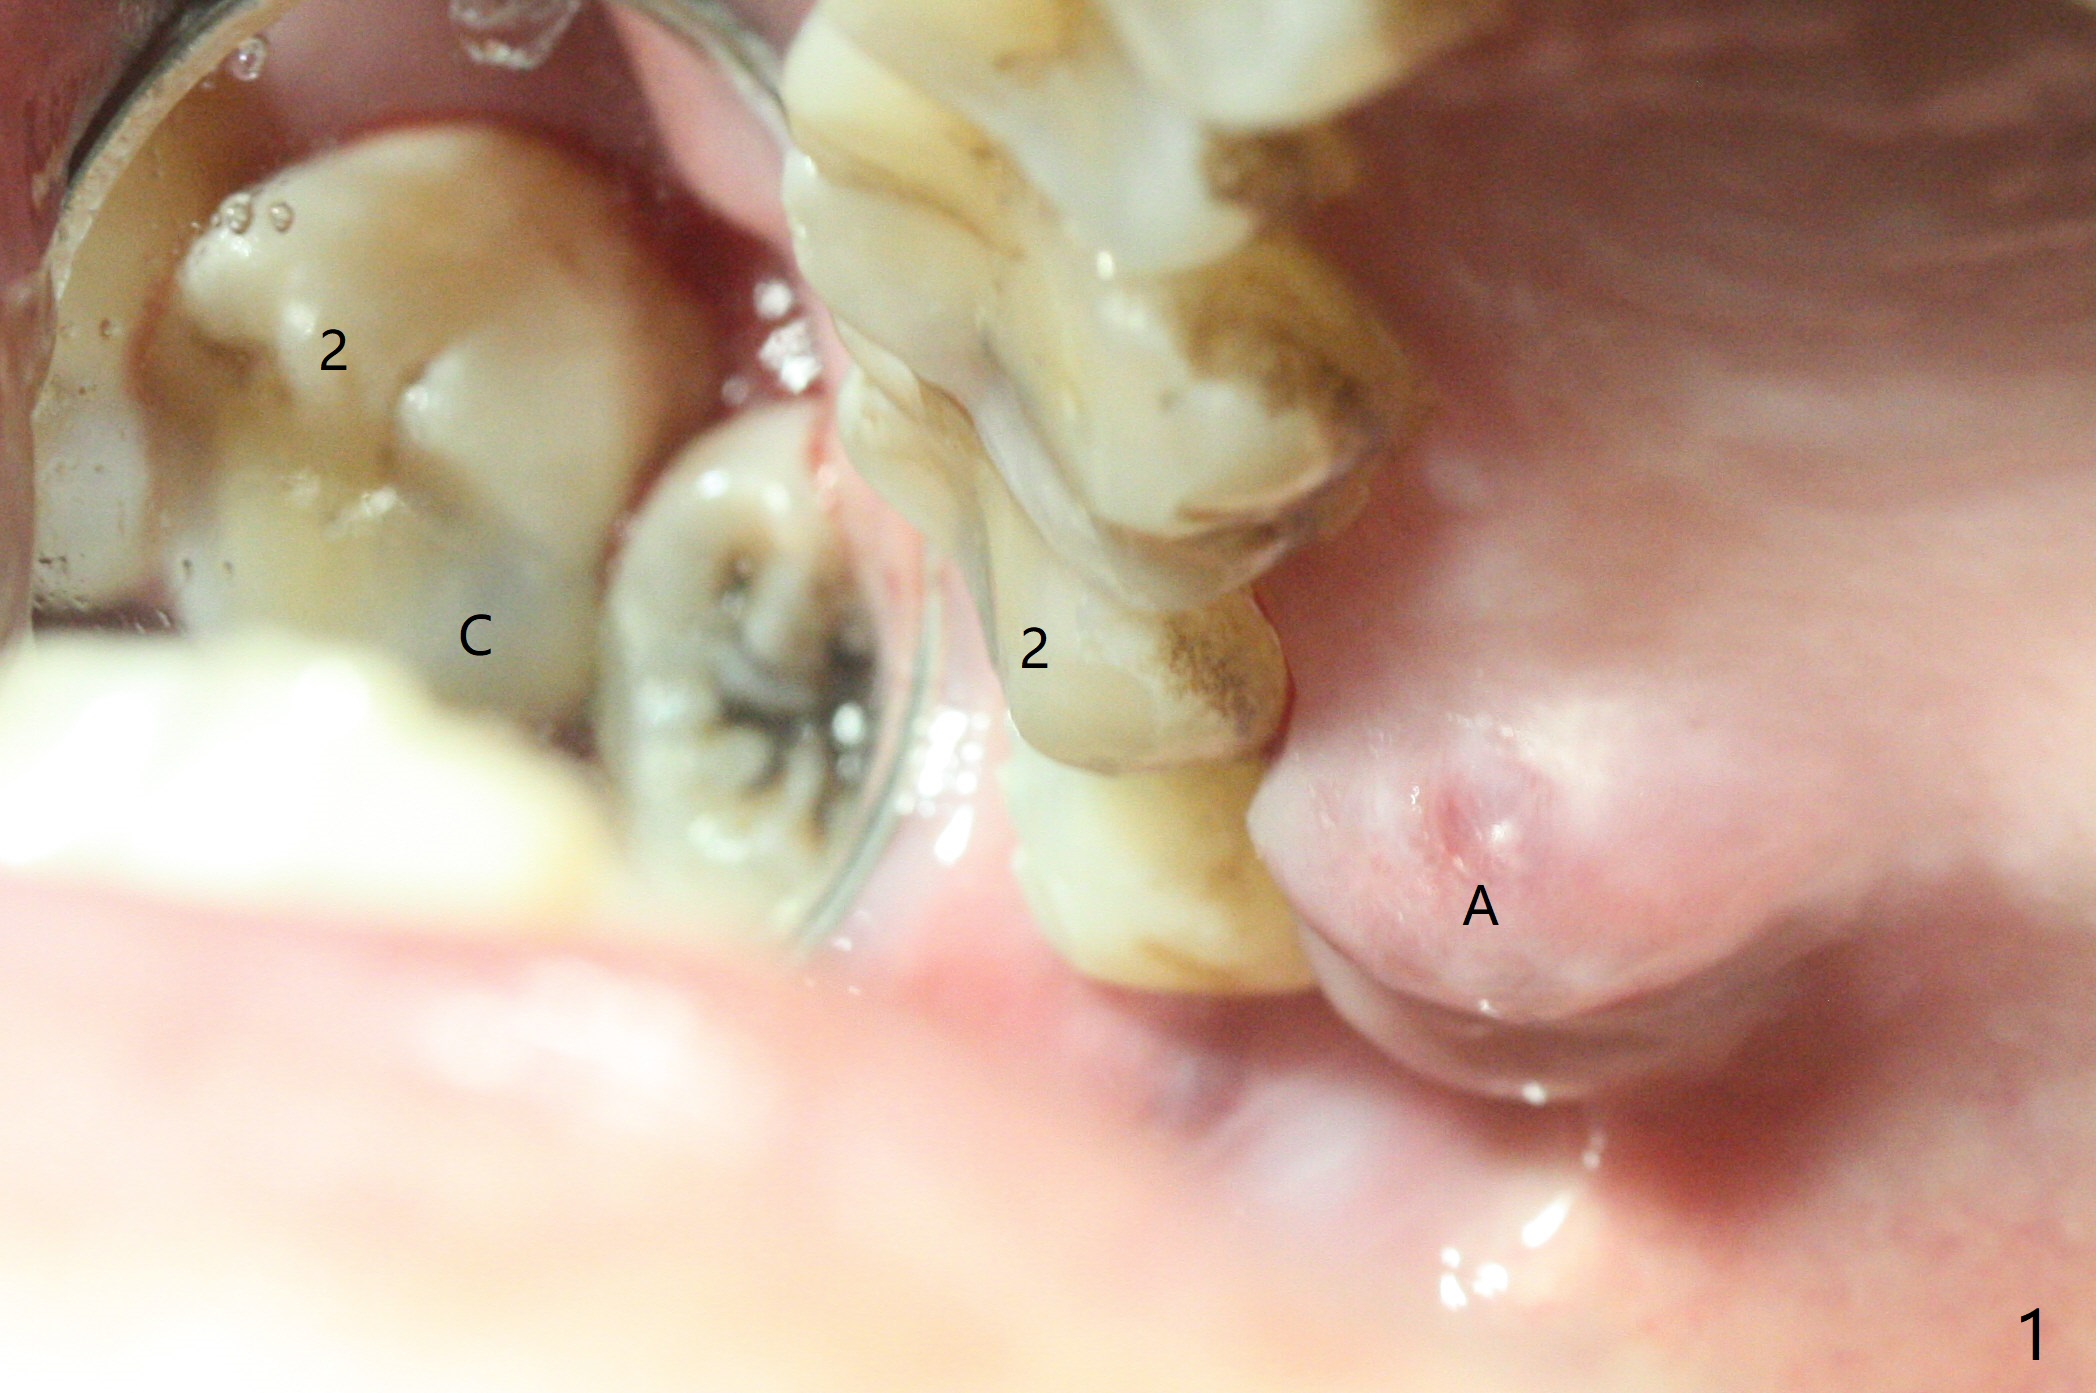

A 62-year-old man has palatal abscess with deep pockets (Fig.1 A) at tooth #2 with DO caries (Fig.2 C). The patient agrees with extraction and bone graft. Preop CT shows the palatal (P) wall defect and buccal (B) socket perforation (Fig.3 *). It should be easy to do sinus lift with the thick sinus membrane (M). To maximize hard tissue regeneration, GEM21S is used to hydrate ground cortical chips (particle size: 125μm – 850μm)) and cortical/cancellous allograft (.5-1 mm) for socket preservation (Fig.4 G) and sinus lift in the buccal socket (^). Due to swollen soft tissue and overpacking, the bone height increases (Fig.5 arrow). The socket opening is closed with GEM Cap and Perio Glue as well as perio dressing.